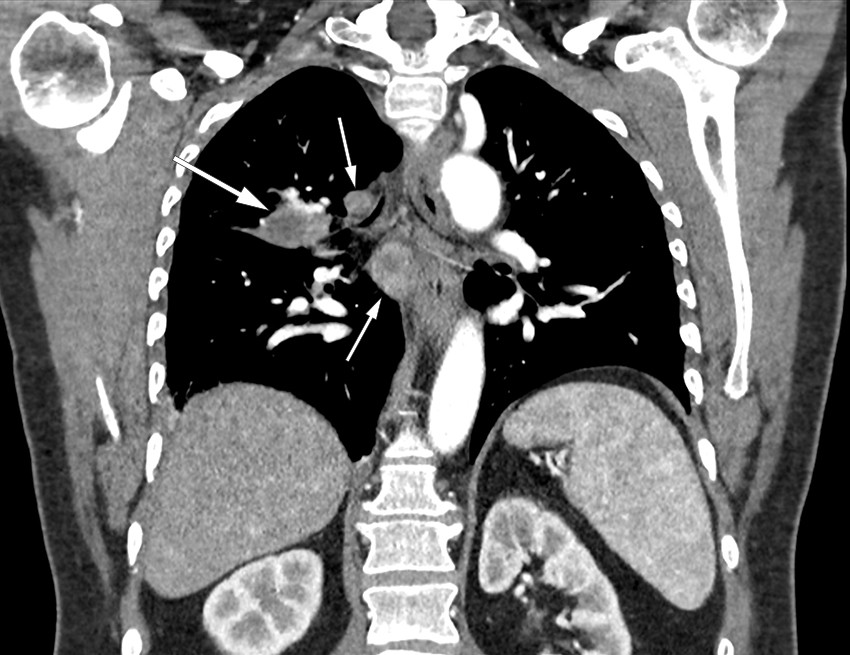

Gjennomgått pneumoni ble vurdert som en mulig diagnose, men grunnet vedvarende nattesvette henviste allmennlegen til CT toraks og abdomen. Bildene viste betydelig mediastinal lymfadenopati og to konsoliderte fortetninger i høyre lunge. Det var sentralt henfall både i fortetningene og lymfeknutene (Figur 1). Funnene ble beskrevet som malignitetssupekte, og fyldige binyrer ble oppfattet som mulige binyremetastaser. Pasienten ble derfor henvist til lokalsykehuset som pakkeforløp lungekreft.

På røntgen toraks ser man ved pulmonal tularemi typisk fortetninger og hilær lymfadenopati. CT toraks viser oftest forstørrede lymfeknuter og konsoliderte, nodulære fortetninger, gjerne perifere og multiple. Et karakteristisk trekk er at lymfeknuter og fortetninger ofte har sentralt henfall, som hos vår pasient (4, 6, 9). Den differensialdiagnostiske utfordringen overfor malignitet, og spesielt lungekreft, er kjent fra litteraturen (4, 5, 7). Det er derfor viktig at radiologer blir informert om eventuell infeksjonsklinikk.